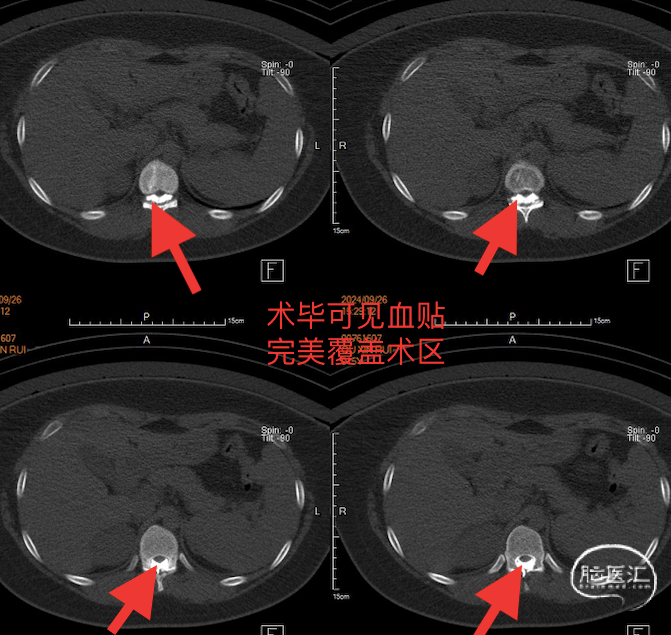

经CT脊髓造影发现瘘口,如上图。

经靶向血贴后,患者仅需卧床24小时即可下床活动,术前体位性症状消失,术后一月复查椎管漏液明显吸收,患者基本没有不适症状。